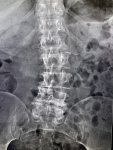

И снова здравствуйте! Сегодня! В этом тредике! Мы будем с вами общатся и играть в доктора! Я буду вам постировать фоточки, а вы угадывать пиздецомы! Я все еще нихуя не успеваю, пытаюсь описать за 25 число, сегодня задержусь наверное после работы опять пытаясь нагнать нагрузку :-(